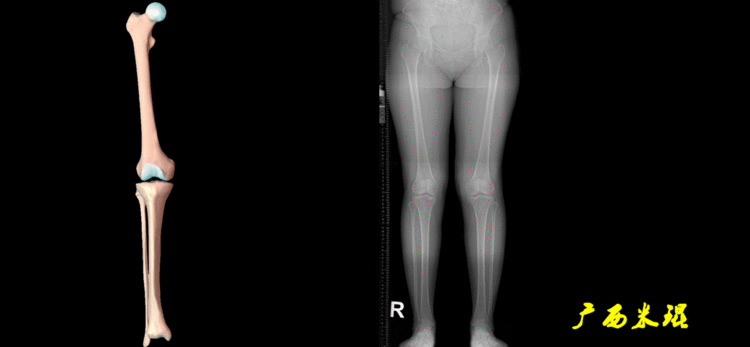

2、画出下肢的轴线确定髋关节、膝关节、踝关节的中心点后,我们才能了解下肢的几个轴线。(1)解剖轴股骨和胫骨的骨干中线为解剖轴,股骨解剖轴和胫骨解剖轴的夹角正常值为174°±1°。

(2)机械轴机械轴是连接近端和远端关节中心点的直线。

机械轴要分前后位及侧位,站立前后位(也就是冠状面)股骨头中心与踝关节中心的连线通过膝关节中心,这是下肢的机械轴线,也就是下肢力线,常说Mikulicz线。冠状面的力线评估在临床工作中最常用、最基础、最重要。

(3)垂直轴也就是下肢的负重轴,它是身体的纵轴线,与地面垂直,由于双髋比双踝的距离宽,所以垂直轴与下肢力线(机械轴)存在3°的外翻。

开始接触时可能我们对这些轴有点混乱,通过下面的这张图片就能清楚的了解下肢几个轴之间的关系。